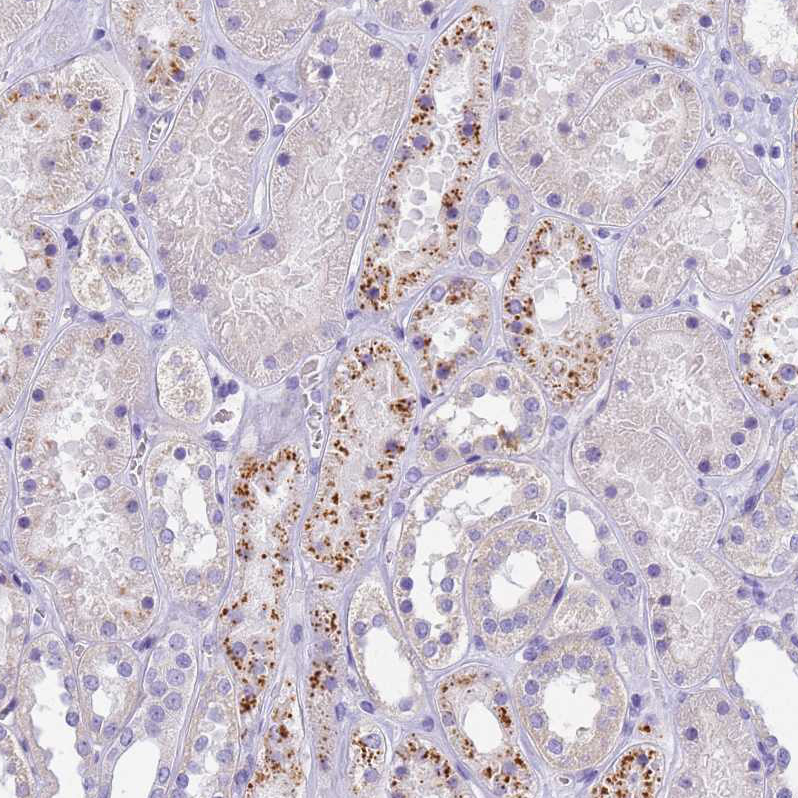

Immunohistochemical staining of human bone marrow shows strong cytoplasm granular positivity in hematopoietic cells.